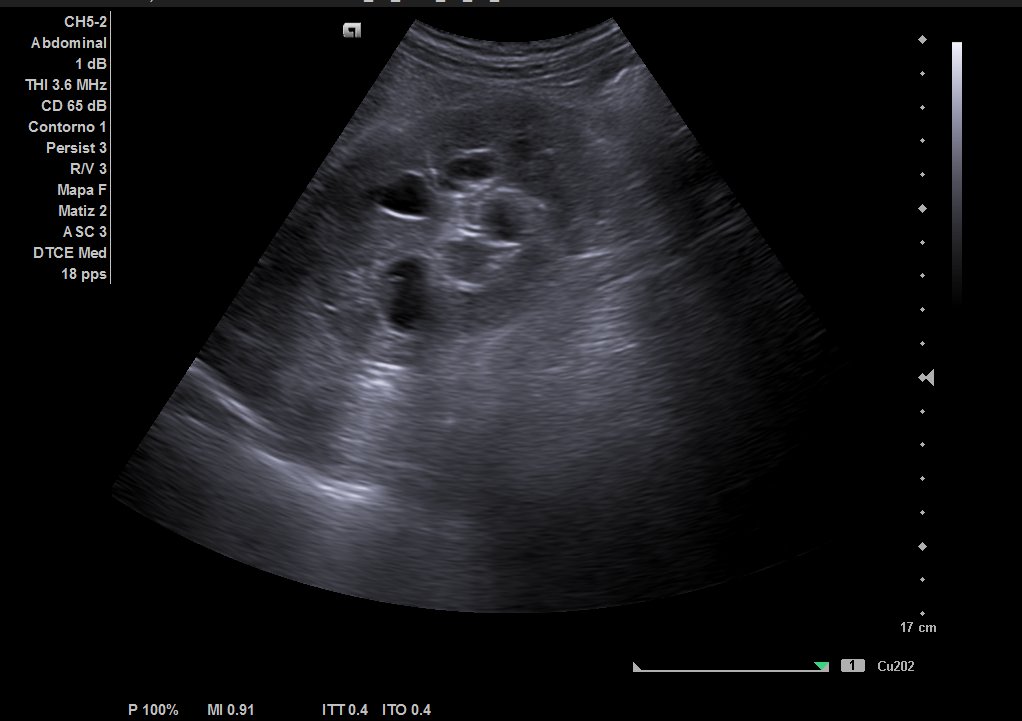

Descripción de los hallazgos ecográficos y las imágenes más relevantes para la resolución del caso

Ecografía urinaria: vejiga bien replecionada, observándose masa en trígono de 20 x 12 mm. Riñón derecho con dilatación pielocalicial moderada, sin hidronefrosis. Riñón izquierdo sin alteraciones reseñables.